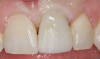

Fig 11. Preoperative photograph.

Figure 11

Achieving outstanding esthetics with implant dentistry is a reality (Figure 11 and Figure 12). Restorative efforts require disciplined steps to attain predictable results. To paraphrase my mentor, Cary Shapoff, DDS, renowned for his knowledge of periodontal disease treatment, bone grafting procedures, and dental implant surgery, implant esthetics is a series of well-planned, well-executed small steps that add up to a successfully restored fixture.